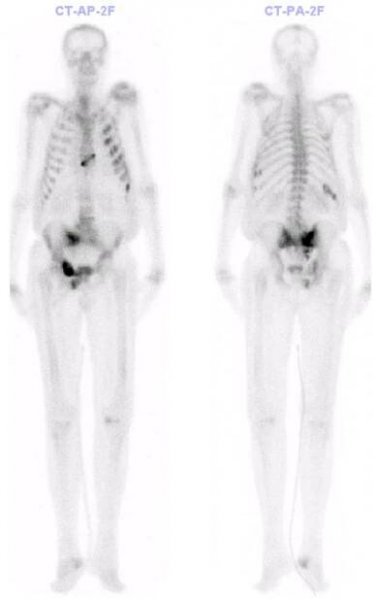

Obr. č. 2: Celotělová třífázová scintigrafie skeletu v kostní fázi.